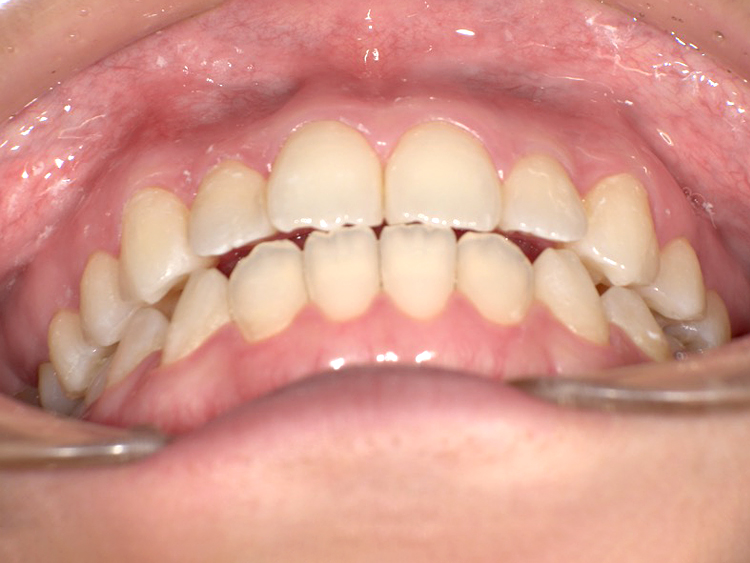

症例4

Before

After

| 主訴 | 上下前歯のがたつき |

|---|---|

| 年齢 | --- |

| 治療 期間 |

約9ヶ月 |

| 治療 内容 |

インビザラインiGoで上下顎の治療。 |

| 治療費 | ¥550,000(税込)/調整料含む |

| 治療のリスク | 矯正終了後は、リテーナーを指示通りに使用し、歯の後戻りを防ぐ必要があります。 |